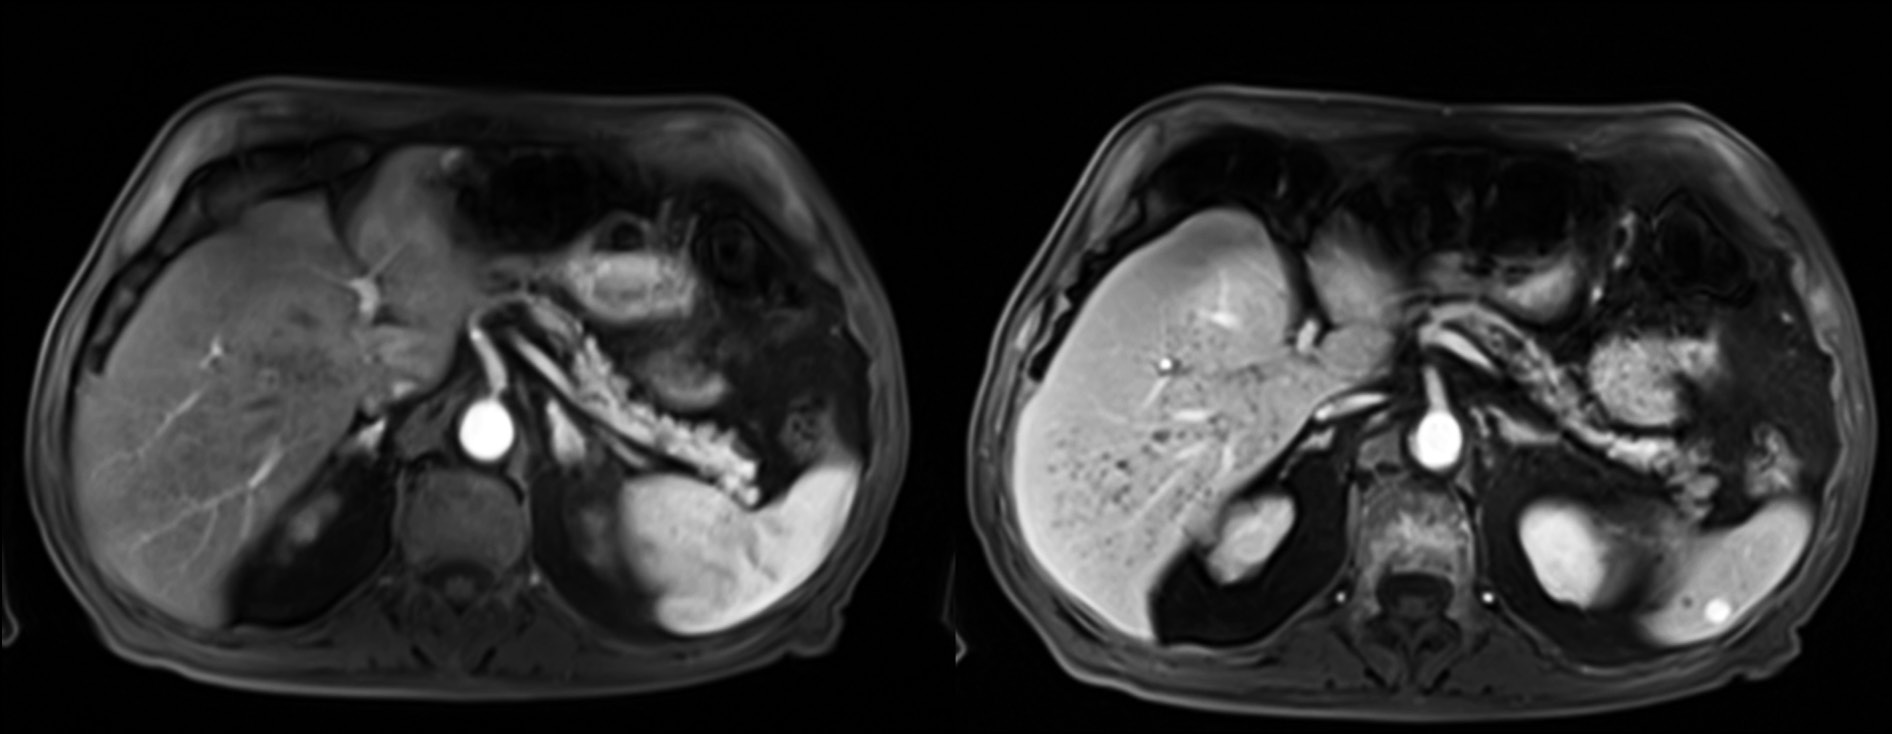

The dynamic study after contrast administration did not show enhancement in the arterial and venous phases (Fig. 5).

Fig. 5. Axial MRI image with T1 sequence showing hypointense lesions without significant contrast enhancement in the arterial and venous phases.